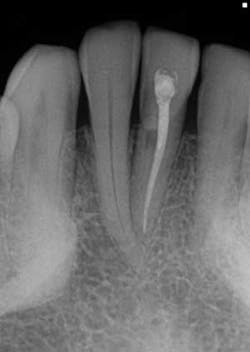

- This is another case of what could easily be misdiagnosed as internal resorption on tooth #No. 24. If you look closely in Figure 7, the outline of the canal can be seen.

- In Figure 8, the lesion is advanced significantly (one-and-a-half years had gone by) the irregular borders and moth-eaten appearance is easily observed.

- Definitive diagnosis: external resorption.